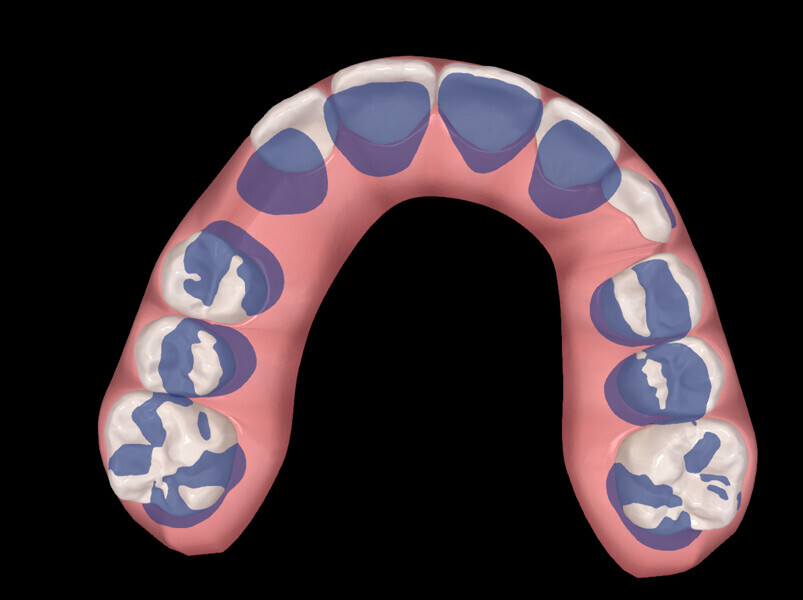

The digital treatment plan (ClinCheck) provided 18 aligners in each arch. The treatment objectives were focused on aligning and levelling the mandibular arch without excessively proclining the mandibular incisors, in order to control the Class III skeletal malocclusion by means of interproximal reduction and slicing of tooth #85. In the maxillary arch, the treatment plan focused on space creation for tooth #13 by distal rotation of the maxillary right molar and mesialisation of the maxillary right lateral incisor simultaneously to centre the midlines. Class II elastics were planned to control distal movement on the right side, and triangular elastics on the high canine were planned on the left side with button cutouts for the aligners. Lateral and posterior maxillary torque were planned to be close to 0° to achieve wider arch design and ideal intercuspation. No digital over-engineering was planned in the set-up, and lingual attachments according to personal preference were placed in the maxillary arch for aesthetic and biomechanical reasons (Figs. 15–19). Eruption compensation for tooth #13 was employed. Because of the age of the patient, the aligners were changed every seven days over the treatment period of less than five months.

At the end of the first stage of aligner treatment (Figs. 20–24), the auxiliary phase began with the bonding of two MTAs on the maxillary right premolars. A 0.016-in Australian archwire, shaped into a cantilever configuration, was then inserted into the MTAs, and a cutout was created on the final aligner. To prevent rotation, the archwire was cinched distal to tooth #15 and the cinch covered with composite.